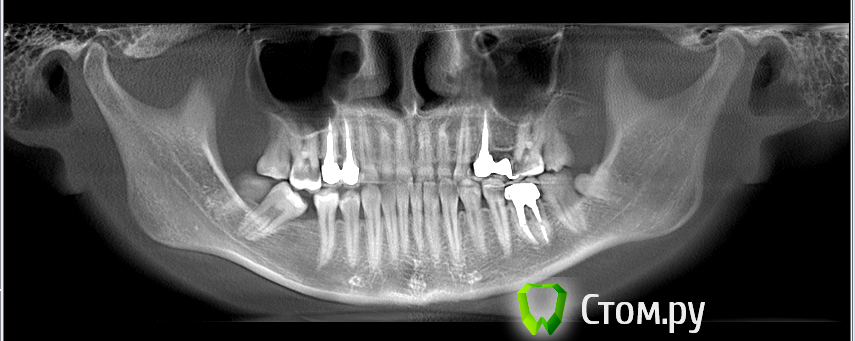

Alessa Опубликовано 9 апреля, 2014 Поделиться Опубликовано 9 апреля, 2014 (изменено) Здравствуйте, уважаемые Врачи!Мне 24 года. Три последних года иногда щелкает челюсть справа. Ощущение, что сустав в неправильное положение встает. И прежде чем открыть рот, приходится челюсть выдвигать немного влево, потом опять вправо, и только тогда рот широко откроется. Недавно была у стоматолога, сделали компьютерную томографию, лечили зубы. Выявили глубокий прикус. Говорят, надо исправлять, иначе стираются зубы. Также, 3 года назад, у меня прорезался восьмой зуб снизу справа, примерно тогда и начала щелкать челюсть. Но не хочется грешить на один-единственный восьмой зуб. Сейчас я контролирую свою челюсть и знаю когда она в правильном, а когда в неправильном положении. Поэтому могу открыть рот и даже не щелкнуть. Болей никаких нет.Была у челюстно-лицевого хирурга, он написал диагноз: переднее вправляемое смещение суставного диска. Ситуация в моей полости рта: пломбы фотополимерные, 3 коронки на жевательных зубах. Отсутствует зуб, нижняя 6-ка справа. Удалили в 2004 году. Седьмой и восьмой зубы справа снизу сдвинулись в направление пятого зуба, седьмой даже наклонился немного. Ещё, отсутствует верхняя 6-ка слева. Коронки ставили давно, в 2006 году.Была у врача здесь, в Омске. Сказали, есть рецессия десны и это плохо. 17 апреля будет совместная консультация хирурга и двух ортодонтов. Изначально я пришла с жалобами на сустав, и предположением, что это всё из-за неправильного прикуса и неправильной окклюзии, раз отсутствует зуб. Жалоб к прикусу нет, он мне не мешает. Но когда я выдвигаю свою челюсть немного вперед, из глубокого в нормальный прикус, то сустав встает в нормальное положение. Соответственно, когда челюсть "уезжает" назад, сустав встает в неправильное.Мои вопросы:1. Может ли, что кость атрофировалась,осела, на месте удаленного зуба, и из-за этого щелкает челюсть? 2. Можно ли сдвинуть 7-ой и 8-ой зубы так, чтобы 7-ой встал на место шестого?Ортодонт, к которому я обращалась говорит, что можно, но это будет очень долго. А если не получится, у меня 7-ой зуб не выпадет? А то на месте удаленного шестого может быть атрофия кости?3. Поднимется ли у меня 6-ой зуб справа сверху после имплантации шестерки снизу, или его вправлять микроимплантом?4. Какие предпочтительные брекеты в моем случае? 5. Есть вероятность резорбции корней зубов? Я этого боюсь. И так своих зубов мало осталось.6. И есть ли вероятность того, что залеченные каналы под коронками как-то «испортятся» после ортодонтии? Или пломбировочный материал выйдет за верхушку корней? Это опасно для зубов?7. Если предложат, делать ли операцию по рецессии десны? И если делать, то после ортодонтического лечения или до? Ортодонт сказала, что у меня там что-то тонкое ( вроде сама десна тонкая) и поэтому рецессия, от природы получается такая ситуация. Ну я сколько себя помню всегда такие десны были. Спасибо за прочтение моей истории! Уважаемые Врачи, интересны Ваши мнения!Фото и снимок КТ прилагаю.На одном из фото я зубы специально поставила в прямой прикус, чтобы показать какое пространство свободное справа. И справа же сустав щелкает. Изменено 9 апреля, 2014 пользователем Alessa Ссылка на комментарий

Skip Опубликовано 12 апреля, 2014 Поделиться Опубликовано 12 апреля, 2014 Из положения прямого прикуса щелчка нет ни при открывании, ни при закрывании рта. Обычно в этом положении нижней челюсти (прямой прикус) изготавливается ортотик, т.е. в положении кпереди от щелчка и когда происходит вправление суставного диска. И удерживать это положение, как можно дольше, обычно около 6 мес., но лучше 12. Выглядит это примерно так: До лечения (глубокий скелетный прикус): http://i7.pixs.ru/storage/4/7/2/Untitled1j_6529039_11667472.jpg С ортотиком: http://i7.pixs.ru/storage/4/8/7/Untitled2j_5380420_11667487.jpg И в завершении лечения проводится этап стабилизации этого положения нижней челюсти на уровне зубов с помощью брекетов: http://i6.pixs.ru/storage/4/9/5/Untitled3j_9031618_11667495.jpg Теперь ответы на вопросы. 1. Может ли, что кость атрофировалась,осела, на месте удаленного зуба, и из-за этого щелкает челюсть? В позиционировании нижней челюсти кзади и, соответственно, такому же положению мыщелка в суставной впадине выноваты Ваши верхние передние резцы, которые подвёрнуты вовнутрь. Потеря 6-го зуба и наклон 7-го сейчас только усугубляют эту ситуацию. 2. Можно ли сдвинуть 7-ой и 8-ой зубы так, чтобы 7-ой встал на место шестого? Нет. Целесообразней будет удалить 8-ой и выпрямить 7-ой, а затем на месте 6-го установить имплантат с коронкой. 3. Поднимется ли у меня 6-ой зуб справа сверху после имплантации шестерки снизу, или его вправлять микроимплантом? Это вопрос чисто технический, так сказать, и меня бы это меньше всего волновало сейчас. 4. Какие предпочтительные брекеты в моем случае? Успех зависит не от этого. 5. Есть вероятность резорбции корней зубов? Я этого боюсь. И так своих зубов мало осталось. Вполне вероятно, если врач переусердствует с приложенными к зубам ортодонтическими силами. Но, в литературе встречаются сведения и о какой-то генетической особенности, предрасполагающей к такому явлению. 6. И есть ли вероятность того, что залеченные каналы под коронками как-то «испортятся» после ортодонтии? Или пломбировочный материал выйдет за верхушку корней? Это опасно для зубов? Хорошо запломбированные каналы у зубов и отсутствие осложнений не являются противопоказанием к ортодонтическму лечению, но что-то гарантировать всегда сложно и эти риски Вы должны разделить с Вашим доктором. 7. Если предложат, делать ли операцию по рецессии десны? И если делать, то после ортодонтического лечения или до? Если будет такая необходимость, то всё только после ортодонтии. 3 Ссылка на комментарий

Skip Опубликовано 21 апреля, 2014 Поделиться Опубликовано 21 апреля, 2014 Когда делала ТРГ, зубы полностью сомкнула. Как раз в таком положении, у меня правый сустав встает в неправильное положение, либо суставной диск, не знаю. Вообще, в жизни, в обычном положении, когда рот закрыт, верхнюю и нижнюю челюсть не смыкаю. Ну насколько я знаю, в норме у человека зубы друг друга касаться должны только во время еды?Просто посмотрев в интернете снимки ТРГ у людей, смотрю, все с сомкнутыми челюстями. Как раз в процессе еды зубы меньше всего касаются друг с другом, только во время глотания. Не смыкая зубы, Вы рефлекторно охраняете свой ВНЧС, что ночью, во время сна, сложно контролировать. То, что касается ТРГ, здесь как и предполагалось - скелетный глубокий прикус + 2-ой подкласс. При этих обстоятельствах, всегда будет высокий риск развития ДВНЧС, тем более у женщины. 2 Ссылка на комментарий